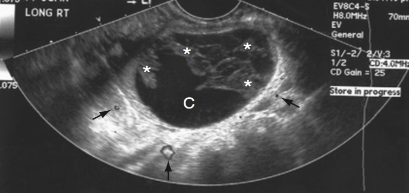

This image displays a

simple cyst